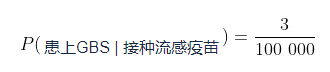

通常情况下,流感疫苗只会稍微增加患上GBS的概率,但2010年暴发了猪流感,如果你在那一年接种了流感疫苗,患上GBS的概率就会上升到3/100 000。在本例中,患上GBS的概率直接取决于你是否接种了流感疫苗。这是一个条件概率的例子。我们将条件概率表示为  ,即在事件

,即在事件  发生的条件下事件A发生的概率。在数学上,我们将在接种流感疫苗的条件下患上GBS的概率表示为:

发生的条件下事件A发生的概率。在数学上,我们将在接种流感疫苗的条件下患上GBS的概率表示为:

这种表示读为“在接种流感疫苗的情况下,患上GBS的概率是十万分之三”。